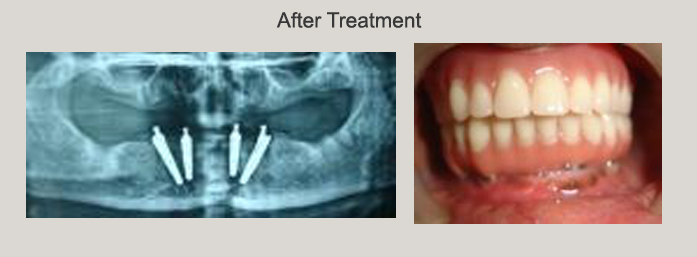

Multiple Implants Both Jaws and Full Mouth Rehabilitation

Lower Jaw All on 4 and Full Mouth Rehabilitation